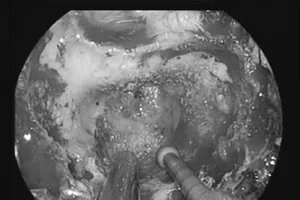

Đau đầu kéo dài, chụp MRI phát hiện u sàn sọ cực hiếm